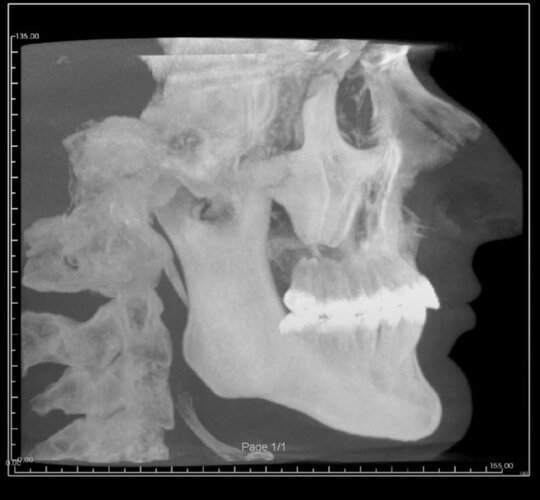

Needing serious advice on what would best surgeries for myself. I’m currently exploring double jaw surgery and rhinoplasty for my subhuman face.

My maxillofacial surgeon has suggested a segmental upper jaw, lower jaw and genioplasty; will cost 12k but I have to wait a year for insurance to cover the hospital side which is 30k… I’m not interested in going overseas for this either.